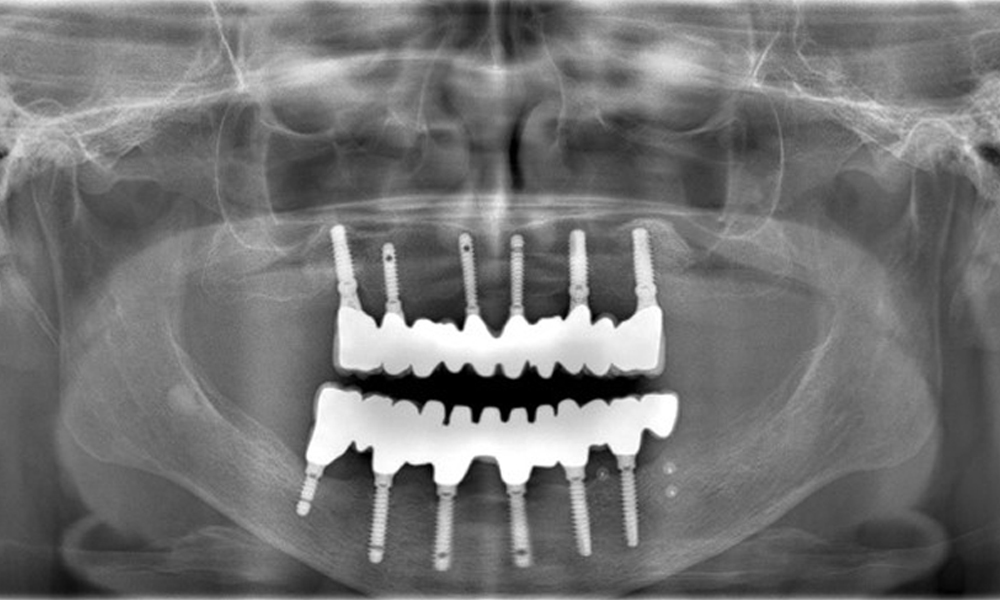

Рентгенографските изображения показват костна резорбция.

Фигура 2: Рентгенографските изображения показват костна резорбция.

Възстановявания: импланти в области 011, 013, 015, 021, 023, 025, 031, 033, 035, 042, 044, 046